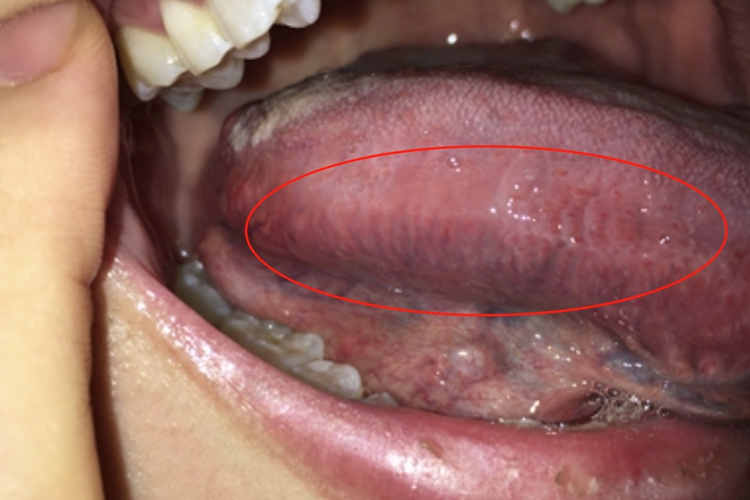

舌炎的损害可发生在舌侧部位,主要表现为局部发红或光滑,并有流涎、进食或咀嚼困难、口内恶臭。同时患者的舌侧部位可有很多紫红色条纹,自觉麻木感、灼热痛等。

舌炎的病因较多,如贫血(包括恶性贫血和缺铁性贫血)、核黄素缺乏症、吸收不良综合征、心力衰竭,以及女性更年期综合征等可引起舌炎。局部刺激因素也能引起舌炎,如不良修复体、牙结石、感染等。